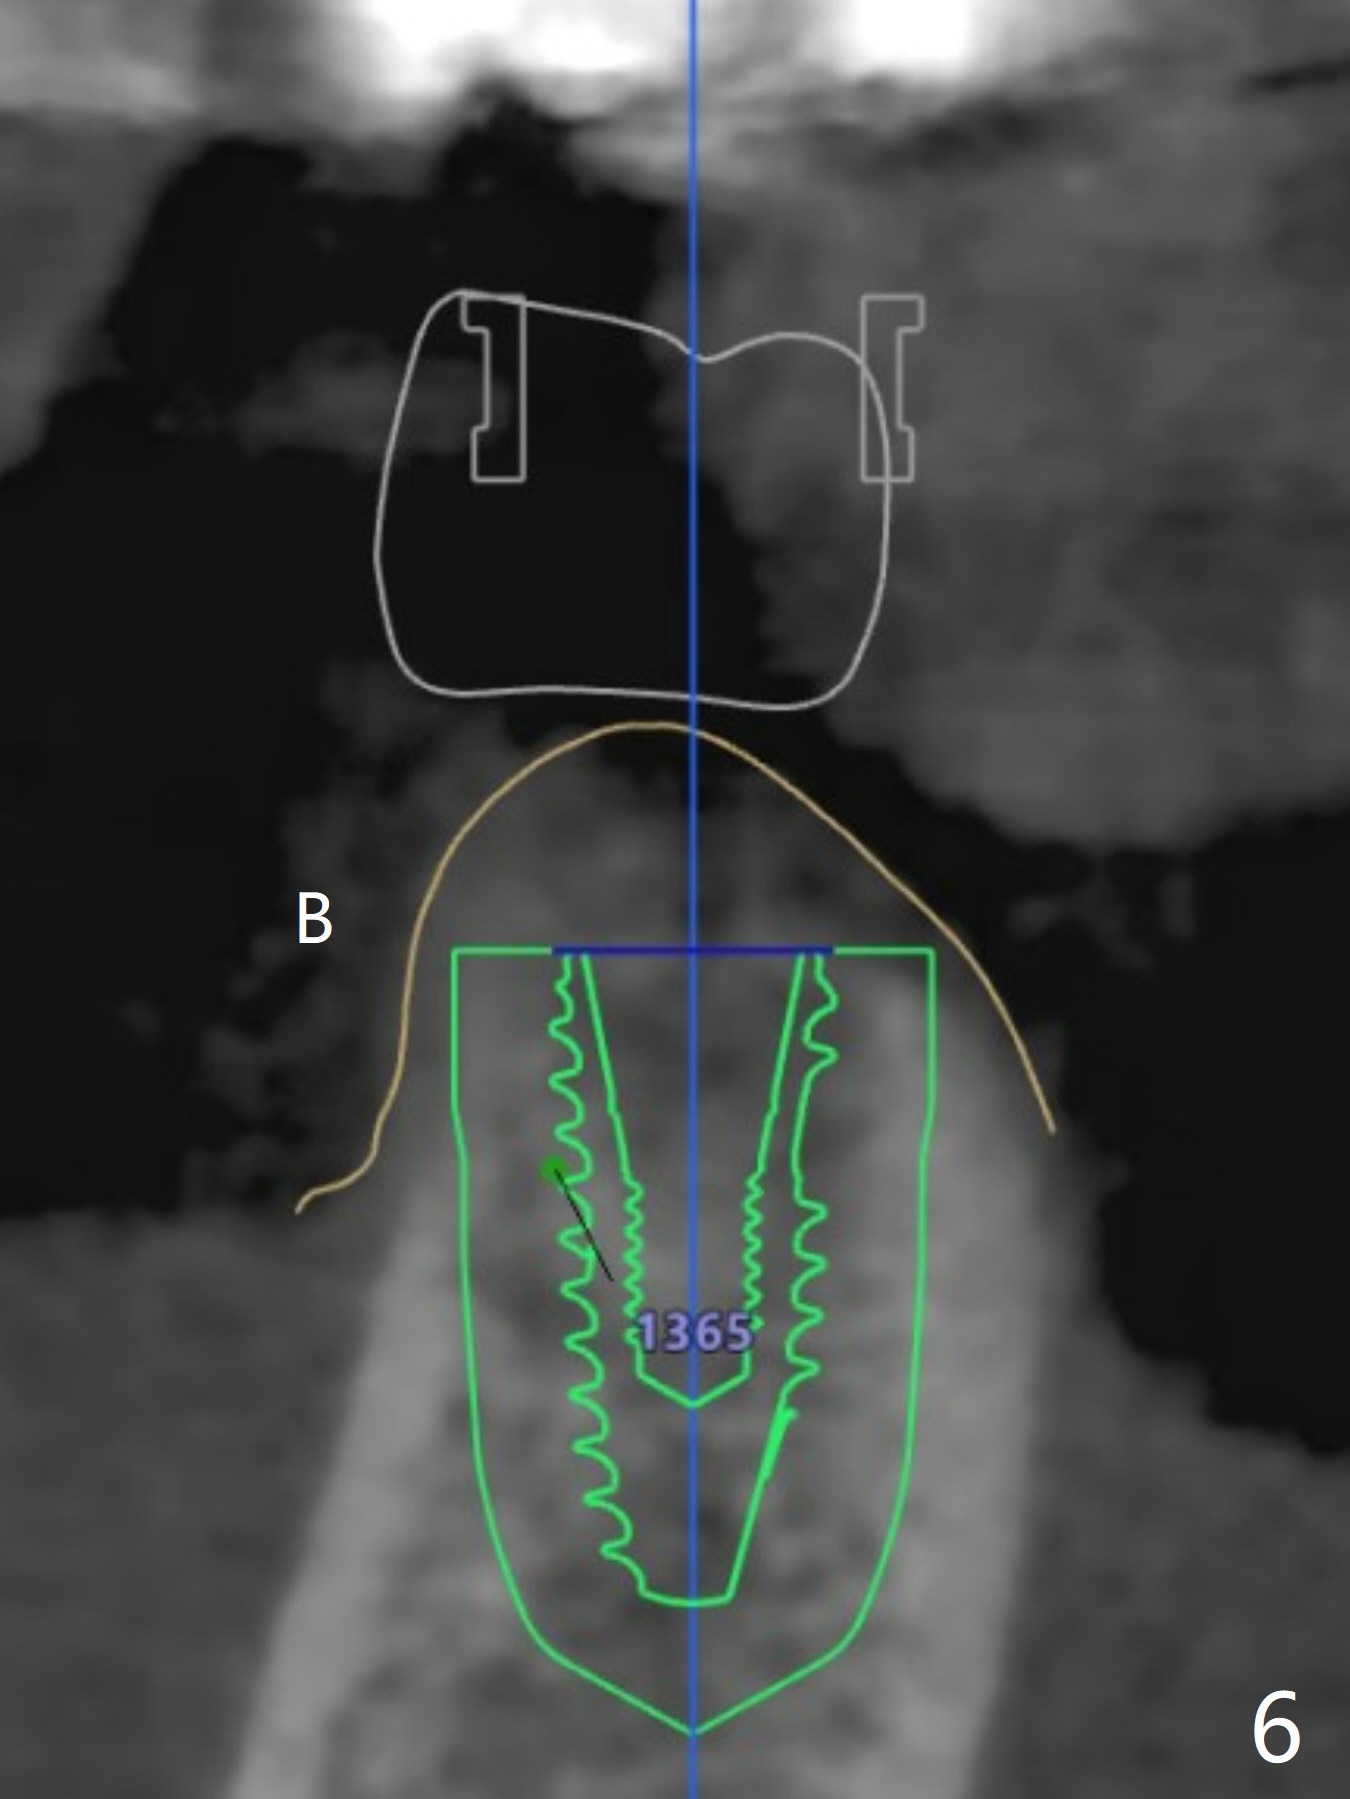

A 77-year-old woman

Return to No Deviation  Xin Wei, DDS, PhD, MS 1st edition 03/04/2021, last revision 05/12/2021